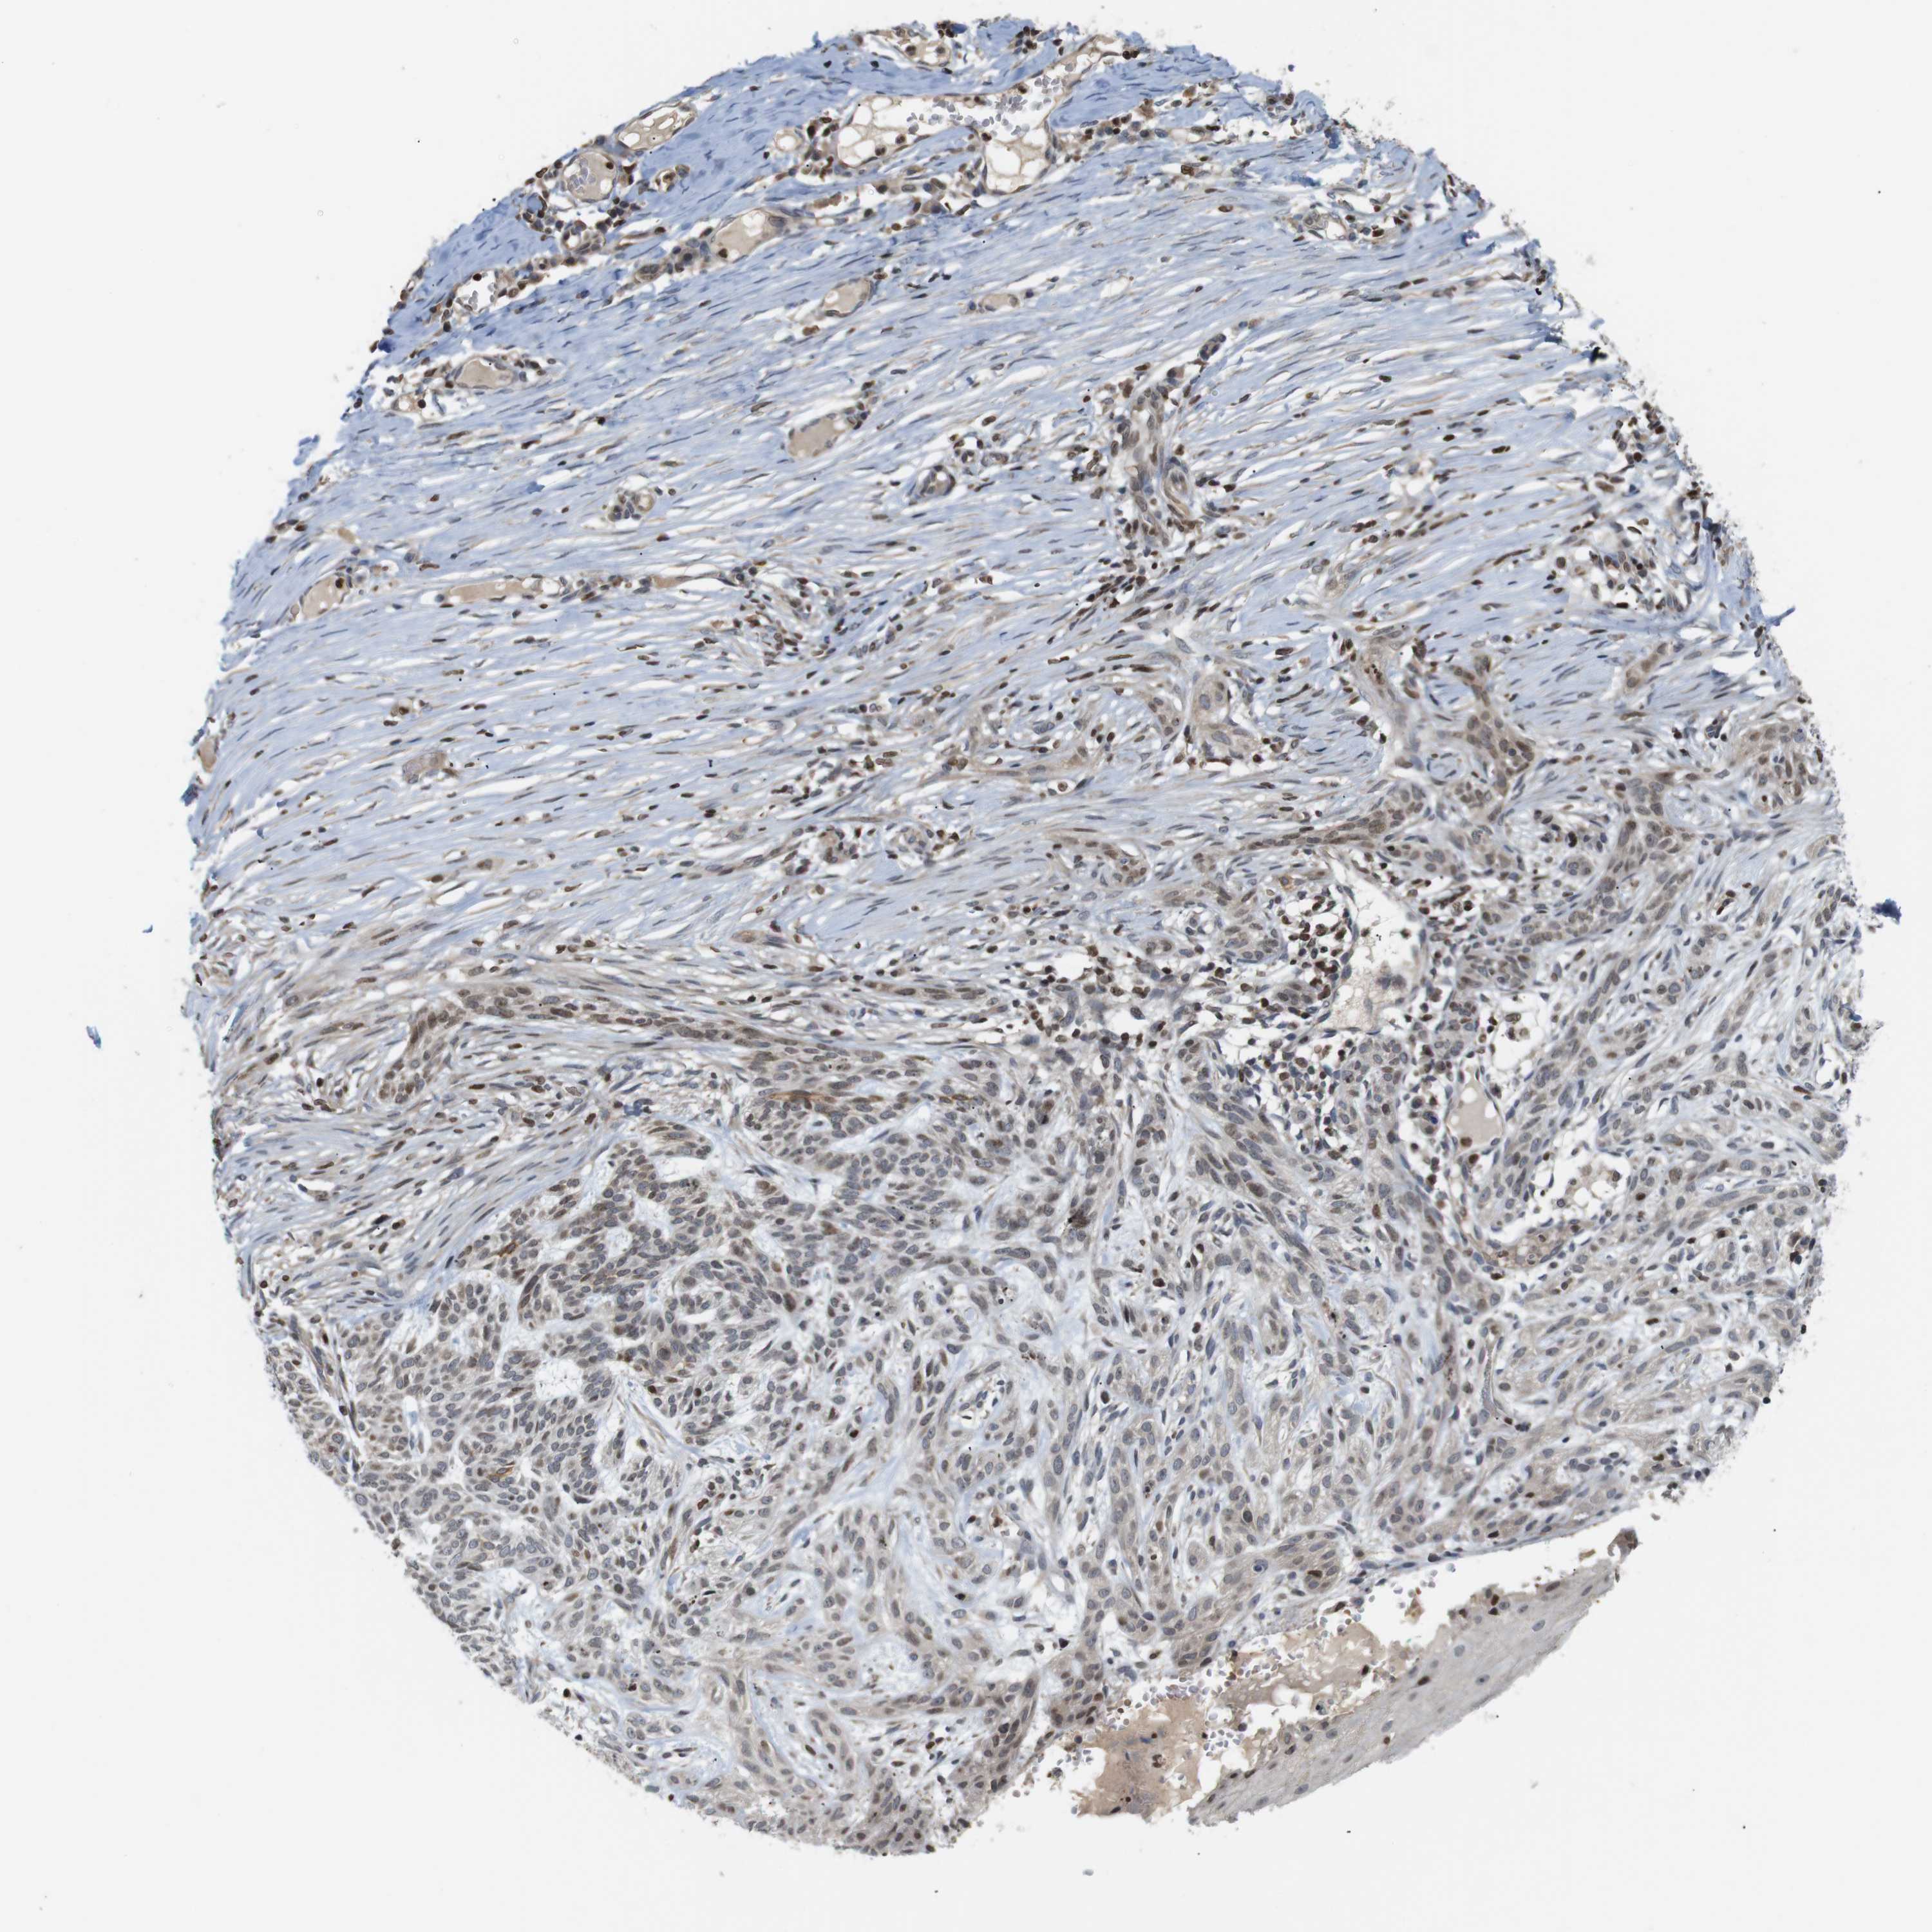

SKIN CANCER - Protein expressioni

A mouse-over function shows sample information and annotation data. Click on an image to view it in a full screen mode. Samples can be filtered based on level of antibody staining by selecting one or several of the following categories: high, medium, low and not detected. The assay and annotation is described here.

Each image is clickable and will lead to virtual microscopy that enables deeper exploration of all samples and also displays staining intensity scores, fraction scores and subcellular localization as well as patient and tissue information for each sample.

Antibody CAB036003

Staining

Low

Intensity

Weak

Quantity

<25%

Location

Nuclear

Basal cell carcinoma

Adnexal tumor, benign